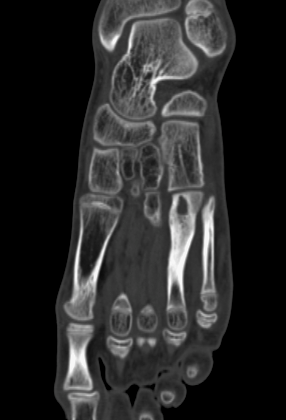

Любого доктора можно быстро подготовить как рентгенлаборанта и дать необходимые знания для оценки рентгенограмм.

Изучение проблемы низкого качества рентгенограмм на Вашем оборудовании.